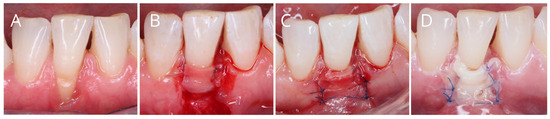

3.2. The Specific Nature of Recession Coverage Procedures in the Context of Potential Postoperative Infection

- Mazzotti, C.; Mounssif, I.; Rendón, A.; Mele, M.; Sangiorgi, M.; Stefanini, M.; Zucchelli, G. Complications and Treatment Errors in Root Coverage Procedures. Periodontol. 2000 2023, 92, e12468. [Google Scholar] [CrossRef]